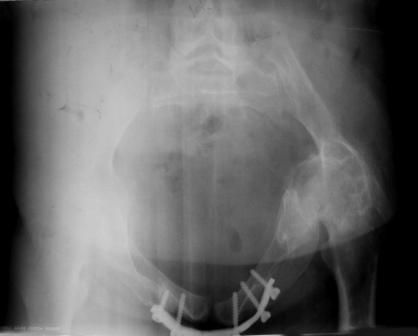

Уважаемые коллеги! Пациентка 32 года с застарелым повреждением таза, после остеосинеза лонного сочленения пластиной. Посоветуйте с выбором тактики и методик лечения.

Февраль 2004 г.

Получила травму в феврале 2004г в г.Лобытнанги ЯНАО Тюм.обл. Через неделю после поступления выполнен остеосинтез лонного сочленения пластиной. 1,5 месяца на скелетном вытяжении. В последующем ходит при помощи костылей с нагрузкой на правую ногу. Имеется нестабильность половин таза, неправильно-консолидированный перелом левой вертлужной впадины, невропатия седалищного нерва слева. В результате невропатии седалищного нерва сформировалась эквинусная установка левой стопы, парестезии по подошвенной поверхности.

Направлена к нам для устранения патологической установки стопы и эндопротезирования левого тазобедренного сустава, также имеется миграция шурупов пластины, фиксирующей лонное сочленение.

Клинически: ходит на костылях с нагрузкой на правую ногу. Левая стопа в эквинусе. Осевая нагрузка на левую н\конечность болезненна в области левого тазобедренного сустава, при прикосновениях к подошвенной поверхности стопы у пациентки чувство зжения. В левом коленном суставе полный обьем движений, в левом тазобедренном резко ограничено отведение и ротация, укорочение левой н\конечности на 2,5 см. При полипроекционной и функциональной Р-графии выявлена нестабильность левого КПС и лонного сочленения, консолидированный в порочном положении поперечный оскольчатый перелом левой вертлужной впадины с центральным смещением головки бедра. Нами выполнена коррекция деформации левой стопы. Планируется выполнить введение 2 канюлированных илиосакральных винтов слева, реостеосинтез лонного сочленения реконструктивной пластиной, после заживления ран - тотальное эндопротезирование левого тазобедренного сустава.